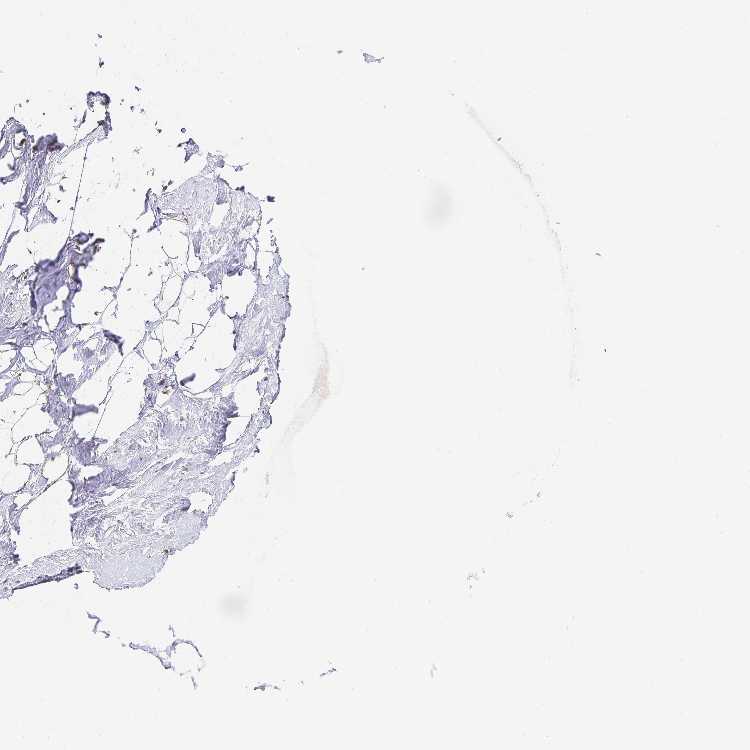

TISSUE PRIMARY DATA BREAST Show tissue menu

BREAST - Antibody stainingi

Antibody staining in the annotated cell types in the current human tissue is reported as not detected, low, medium, or high, based on conventional immunohistochemistry profiling in selected tissues. This score is based on the combination of the staining intensity and fraction of stained cells.

Each image is clickable and will lead to virtual microscopy that enables deeper exploration of all samples and also displays staining intensity scores, fraction scores and subcellular localization as well as patient and tissue information for each sample.

Antibody HPA037589Antibody HPA037590Antibody CAB009846

Adipocytes LowNot detectedNot detected

Glandular cells MediumMediumMedium

Myoepithelial cells MediumMediumMedium